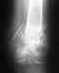

Мне 35 лет. В 2014 году был перелом ключницы в Египте. Там же сделана операция. Поставлена пластина. В 2017 году рассшатался шуруп и вылез. Сделали снимок. Перелом не сросся образовался ложный сустав. В 2017г.сделали операцию по извлечению пластины. Ложный сустав не удаляли.... через полгода появились ноющие боли. Сделали снимок, отправили на операцию по удалению ложного сустава. В больнице снова отговаривал делать операцию... Процент срастания после удаления ложного сустава ключницы 30 в лучшем случае 50 процентов. Операция сложная. Рука подвижная. Живите так. Что делать

Без снимков разговор беспредметный. Абстрактно можно сказать, что если выраженность болезненных проявлений не превышает порог приемлемости, получается себя обслуживать, делать все, что надо, по работе и дома, то действительно можно с операцией не спешить.